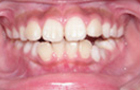

治療前-治療後

飛び出して持ち上がってしまっていた前歯が降りてきました。

横向き寝やうつぶせ、頬杖などに気をつけて治療をし、V字型だった歯並びが本来のU字型になってきました。

これで永久歯を抜かないで治療することができるようになりました。飛び出していた前歯がだんだん咬みあってきました。

まだまだ途中経過ですが、身体がだいぶんまっすぐになってきました。